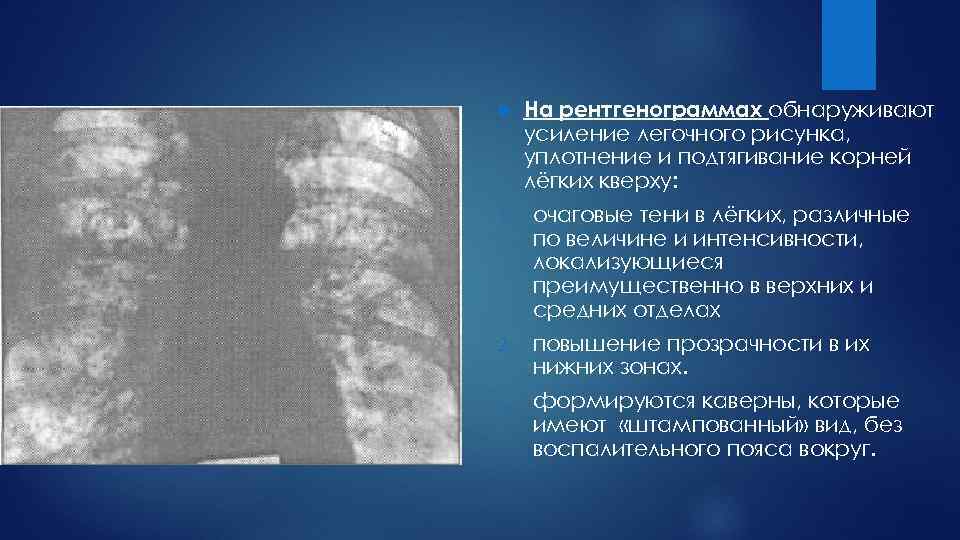

Ячеистая деформация легочного рисунка: медицинская визуализация